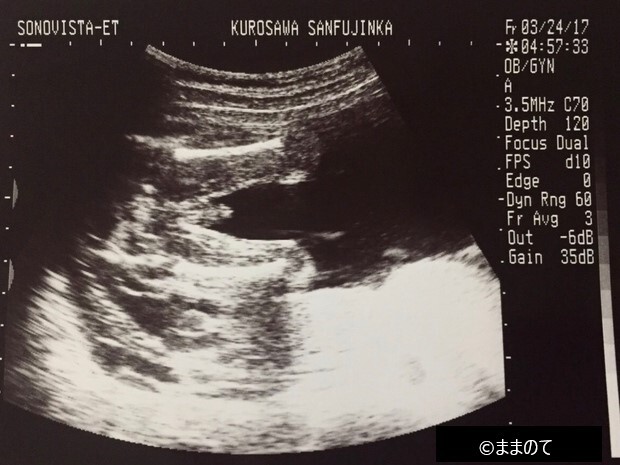

【男の子のエコー】妊娠22週

V字に分かれた2本の足のあいだに、小さな突起物が見えます。陰茎の付け根に陰嚢が薄く写り込んでいるのも確認できますね。